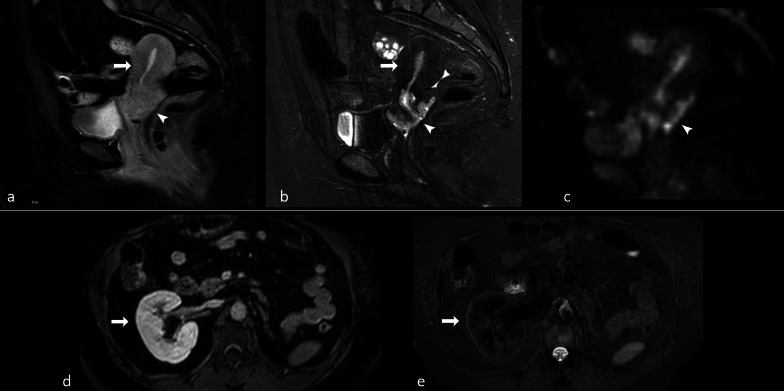

In view of their non-selectivity, STIR sequences are generally not recommended to be used after administration of gadolinium for fat suppression, as both enhanced organs and lesions can show a loss of signal comparable to that of fat (e.g., normal renal parenchyma, Fig. 14d, e) and other sequences are usually preferred [77, 78]. However, this phenomenon could be exploited to better delineate a tumoral lesion in some specific cases. For instance, in case of uterine cancer the exact definition of tumor margins in relation to normal parenchyma is often challenging. It is possible that the usage of STIR sequence following gadolinium administration may lead to a better delineation of the lesion in comparison with conventional contrast-enhanced T1-w. fat-suppressed TSE images, as the correspondence between STIR and diffusion-weighted images seems to suggest (Fig. 14a–c). However, future studies are needed to better clarify these topics.

Fig. 14.

38-year-old patient with cervical carcinoma. On contrast-enhanced turbo spin echo (TSE) T1-w. fat-saturated sagittal image (a) differentiation between normal uterus and cancer is difficult. On sagittal short inversion time inversion recovery (STIR) scan (b) obtained at the same level immediately after TSE sequence, the signal of normal uterus is cancelled and hyperintense cancer is well depicted. There is an optimal correspondence between STIR and diffusion-weighted image (c), where spatial resolution is however lower. Contrast-enhanced gradient echo (GE) T1-w. fat-saturated scan (d) through the right kidney. Contrast-enhanced fast-STIR image (e) obtained immediately after d shows that the signal of renal parenchyma is cancelled since its T1 is equal to that of fat